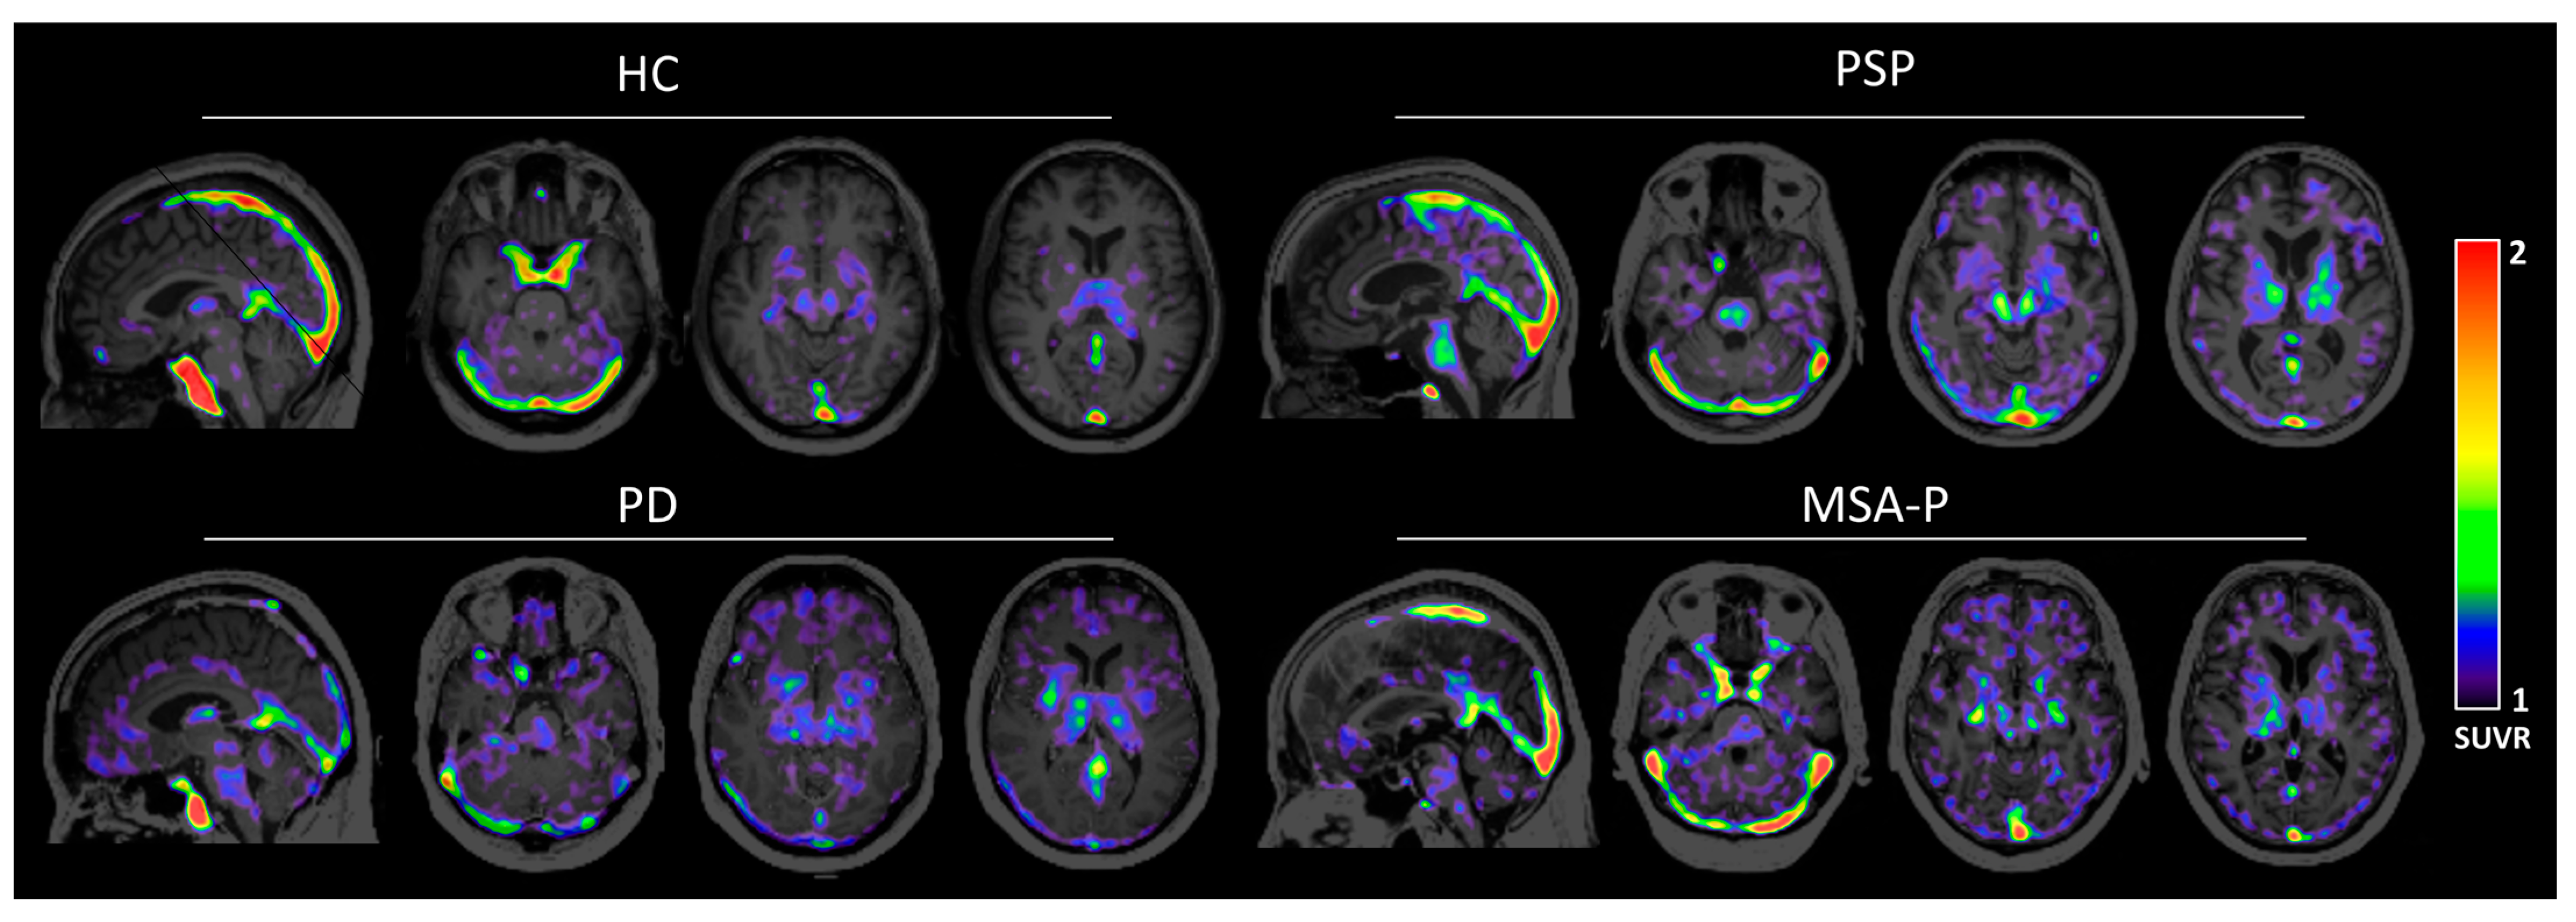

3.2. Human Brain Images of [11C]HY-2-15